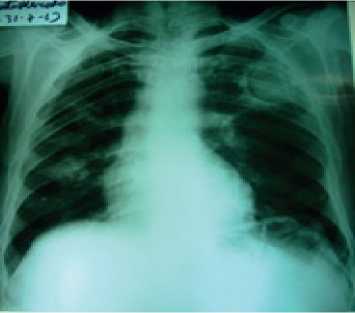

Se realiza una radiografía de tórax PA (Figura 1) donde se evidencia aumento de densidad de aspecto redondeado con hiperclaridades en su interior una localizada en el lóbulo medio derecho y otra de mayor tamaño en el lóbulo superior izquierdo con presencia de imagen en semiluna aérea y presencia de masa intra-cavitaria. Con bordes externos de la lesión de aspecto espiculado y pequeño nódulo pulmonar calcificado basal derecho.

Figura 1. Radiografía de tórax PA.Se evidencia aumento de densidad de aspecto redondeado con hipercla-ridades en su interior una localizada en el lóbulo medio derecho y otra de mayor tamaño en el lóbulo superior izquierdo con presencia de imagen en semiluna aérea y presencia de masa intracavitaria. Con bordes externos de la lesión de aspecto espiculado, pequeño nódulo pulmonar calcificado basal derecho.